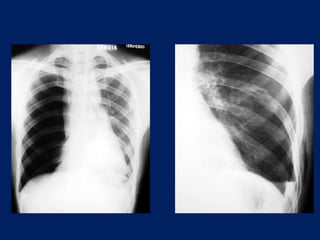

- RADIOGRAFIA DE TORAX.

Derrame pleural

masivo izquierdo

Se aprecia un aumento de la transparencia del lado

correspondiente al neumotórax, con el pulmón retraído

hacia el hilio, dando una forma de muñón característico.